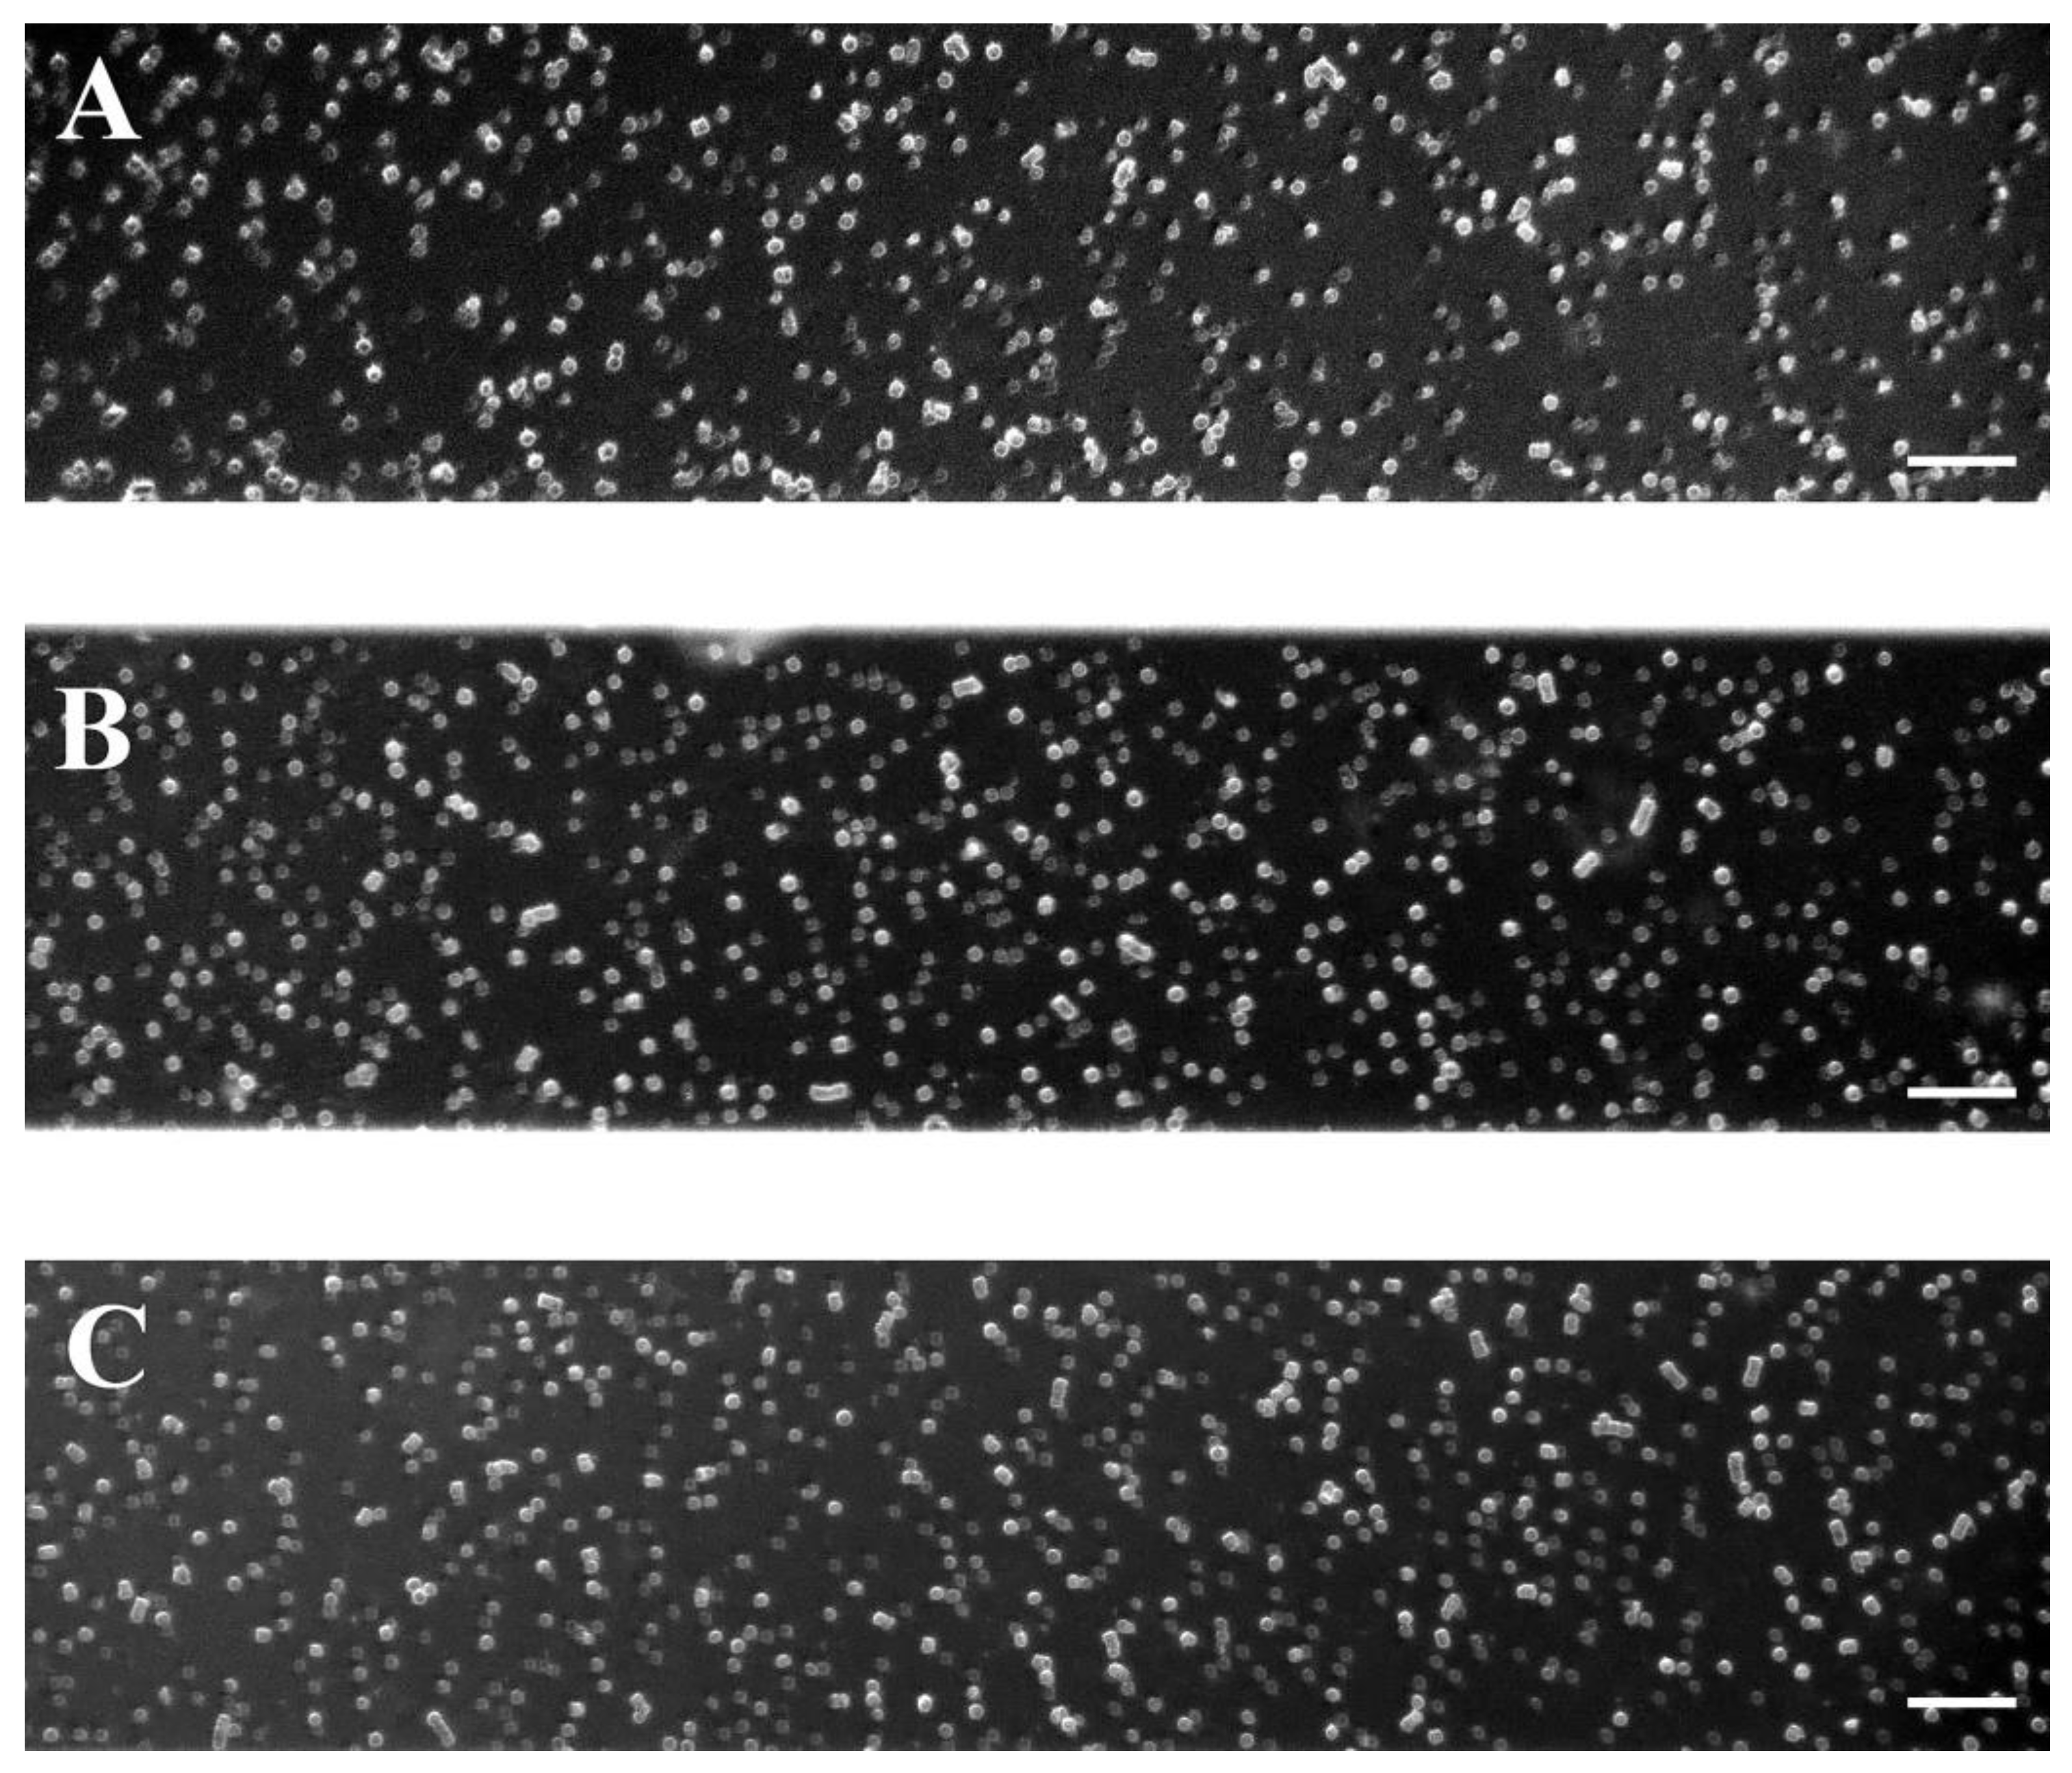

4.6. Microfluidic System and Experiments

4.8. Computational Image Analysis for the Evaluation of the RBC Aggregates